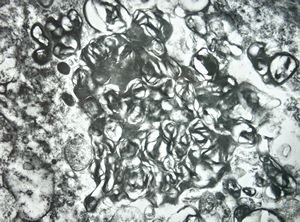

F,68y. | spleen - undefined myelinoid inclusions - clin. susp. leukemia

F,68y. | spleen - myelinoid inclusions - clin. susp. leukemia